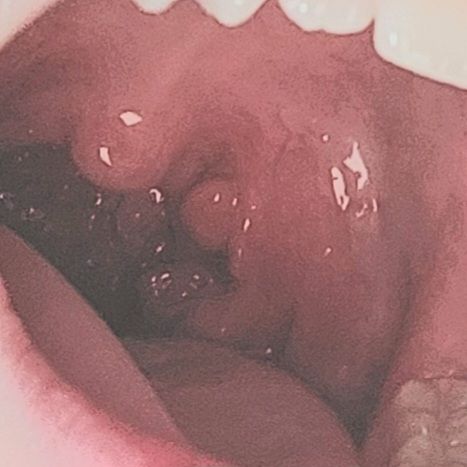

목젖 옆, 안쪽에 돌기같은 것이 많습니다.

한쪽에만 포도알처럼 주렁주렁 있습니다

한 3년전부터 있던 건데 음식물이 사이에 끼어 자주 고생합니다. 하지만 최근에 목감기에 걸린적도 없고, 목이 아프지도 않습니다. 만성염증 같은 건가요?

편도조직이 위치하는 곳이고, 편도가 커진 상태라 보입니다. 사진으로는 염증소견이 보이지 않는 것 같으나 정밀한 진찰을 위해서는 이비인후과 진료가 필요할 것이라 보입니다.